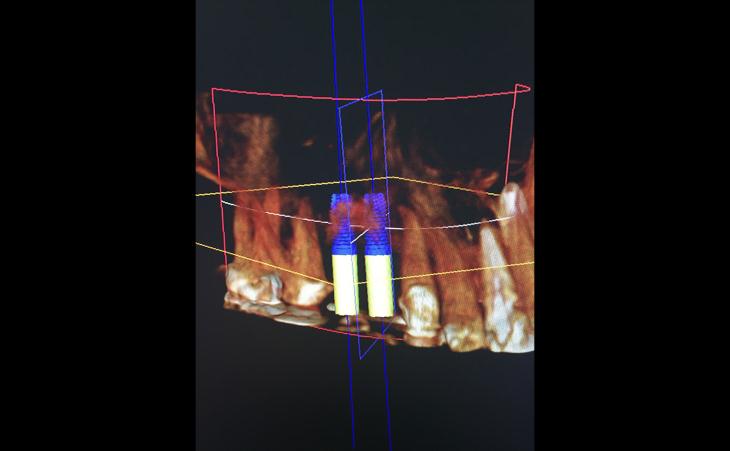

40 year old male with fractured upper left molar. Tooth was extracted, bone was regenerated. Then a surgical guide was made for proper implant angulation and placement. Internal sinus elevation was accomplished in order to avoid a Sinus Lift. An implant was placed and restored.

46 year old male has been missing his upper teeth for years and wore a denture. He had severe dental phobia . Using Advanced guided surgical technique, I was able to plan his entire surgery virtually, create a surgical guide (template) and place his implants in the most ideal positrons. Virtual planning held to shorted surgical time and thus improves technique and recovery.

Pt was missing her front teeth for many years. She did not have enough bone to place implants. I regenerated her jaw bone with a custom bone graft. Then using computer guided implant surgery , placed 2 dental implants to hold new teeth . The case was a success

Patient presents with all upper teeth in state of decay, loose, not able to make a new bridge. This case was planned with a prosthodontics colleague, to extract all upper teeth, place dental implants and immediately, same day, place temporary bridge on the implants so patient can leave with teeth same day of surgery and wear these temporary teeth for approximately 6 months until the implants are healed and final teeth can me made. The implants are placed using a computer guide made ahead of the surgery to assure implants and planned teeth are in the exact planned positions. Dr. Stein and Dr. Koslovsky are among the only oral surgeons with the skill to do this type of complex implant placement.